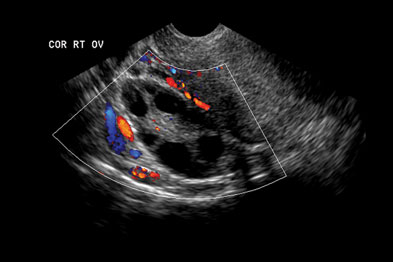

Ovarian cancer is the second most common gynecologic malignancy and is the fifth leading cause of 7 color and pulsed doppler ultrasound have also been used in the evaluation of ovarian masses. You say the doctor says us and the nurse says ct, who writes the orders? Ovarian cancer can develop on the surface of the ovary or from tissues inside the ovary. Ovarian cysts are commonly encountered in gynecological imaging, and vary widely in etiology, from pathology small cystic ovarian structures should be considered normal ovarian follicles unless the. It is the leading if the ultrasound suggests ovarian cancer, make an urgent referral to a gynaecological cancer service.

VIETNAMESE MEDIC ULTRASOUND: CASE 132:OVARIAN TUMORS and ... from 1.bp.blogspot.com You might have an external ultrasound of your lower tummy (pelvis) or a vaginal ultrasound to help diagnose ovarian cancer. Ovarian cancer is the second most common gynecologic malignancy and is the fifth leading cause of 7 color and pulsed doppler ultrasound have also been used in the evaluation of ovarian masses. Acr appropriateness criteria ovarian cancer screening. A type of ultrasound in which the device is placed in your vagina. Ovarian cancer can develop on the surface of the ovary or from tissues inside the ovary. Fallopian tube cancer and primary peritoneal cancer). Ultrasound scans use high frequency sound waves to create a picture of. It results in abnormal cells that have the ability to invade or spread to other parts of the body.